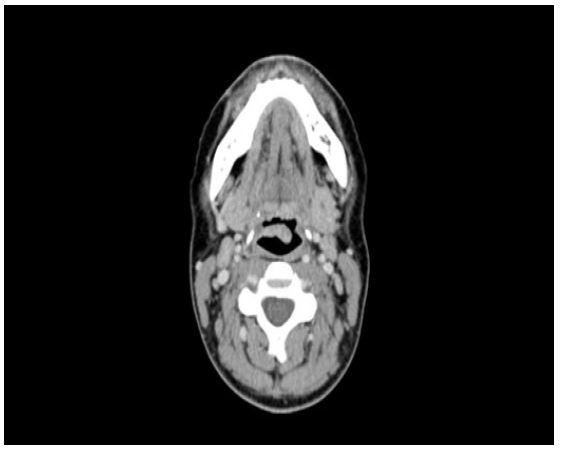

The patient was admitted to the hospital with a diagnosis of pulmonary tuberculosis with laryngeal involvement. A CT thorax performed, showed findings consistent with radiologically established pulmonary tuberculosis with upper zonal predominance (Figure 2). A CT neck on the same day revealed mild thickening of the epiglottis, particularly on its cranial aspect, and mild superficial enhancement at the level of the supraglottis (Figure 3).

Figure 3: CT Neck demonstrating moderate swelling of the epiglottis, more pronounced on the left side than the right.